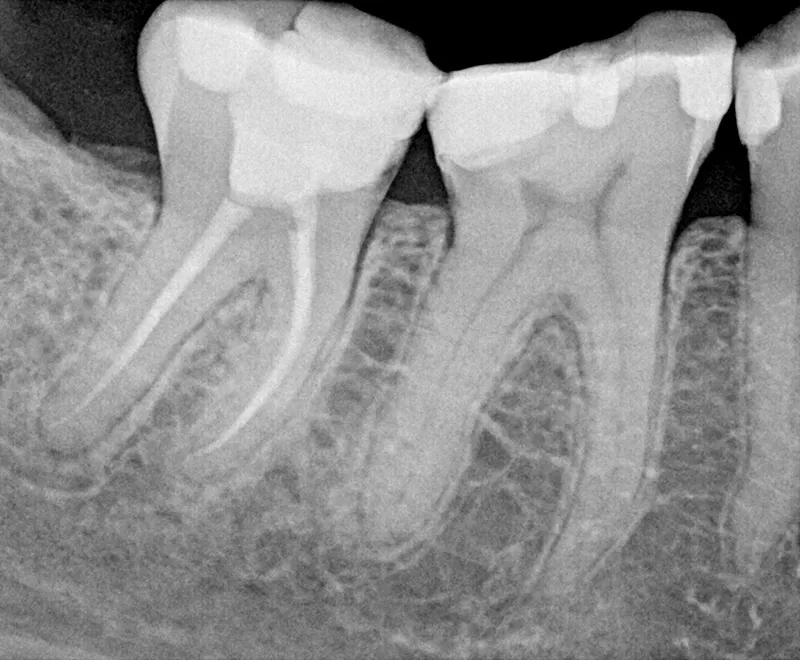

Root canal before

Before